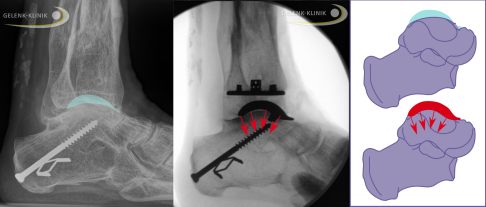

Damit die Prothese am Sprunggelenk lange hält, müssen Fehlstellungen und Bandschädigungen behoben werden. Wichtigstes Ziel ist, eine senkrechte Belastung der Implantate beim Stehen und Gehen zu erreichen. Nur so verteilt sich die hohe Gewichtsbelastung auf der Sprunggelenksprothese gleichmäßig.

Mögliche Fehlstellungen erkennt der Arzt bei der klinischen Untersuchung sowie durch die Podometrie und die orthopädische Ganganalyse. Durch bildgebende Verfahren wie die digitale Volumentomographie (DVT) und Röntgenaufnahmen unter Belastung des Sprunggelenks (im Stehen) lassen sich die genaue Position und die Stellung der knöchernen Komponenten analysieren. Festigkeit und Beweglichkeit des Sprunggelenks werden im Rahmen der klinischen Untersuchung geprüft.

Achskorrektur: Eine stabile Prothese setzt eine gerade Sprunggelenksachse voraus

Für eine gute Haltbarkeit der Prothese ist es wichtig, die meistens nach einem Unfall entstandenen Fehlstellungen und Bandschädigungen zu beheben. Ebenso wie das natürliche Gelenk bedarf das künstliche Sprunggelenk natürlicher Belastungslinien.

Fehlstellungen, Bandinstabilitäten und mangelhafte Knochenqualität verhindern das stabile Einwachsen der Sprunggelenksprothese. Auch anlagebedingte fehlgeformte Füße, ein Plattfuß oder ein Hohlfuß, beeinflussen die Form einer Arthrose maßgeblich und müssen bei der Therapieentscheidung einbezogen werden. Je stärker die verbleibende Achsabweichung, umso kürzer ist die zu erwartende Lebensdauer der Sprunggelenksprothese. Der Spezialist für Fuß- und Sprunggelenk kontrolliert daher stets die Stellung der Prothesenkomponenten in Bezug auf die Beinachse, die Rückfußstellung anhand der Fersenbeinposition, das Fußlängsgewölbe sowie die Ausrichtung relativ zum Vorfuß.